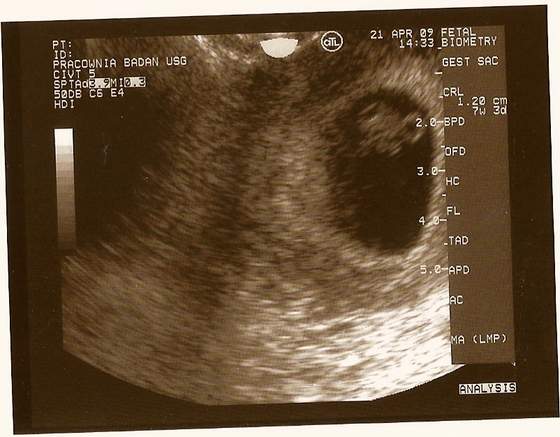

wczoraj wieczorem byłam u gina zrobił mi usg i wiecie co widziałam jak bije serduszko

nie mogłam w to uwierzyć.

Jestem teraz w 7 tygodniu i 4 dzień, a mój dzidziuś ma 1.34 cm

lekarz powiedział ze jest duzy ale nie mam sie czyma martwić bo jest wszystko w jak najlepszym porządku :-):-):-)